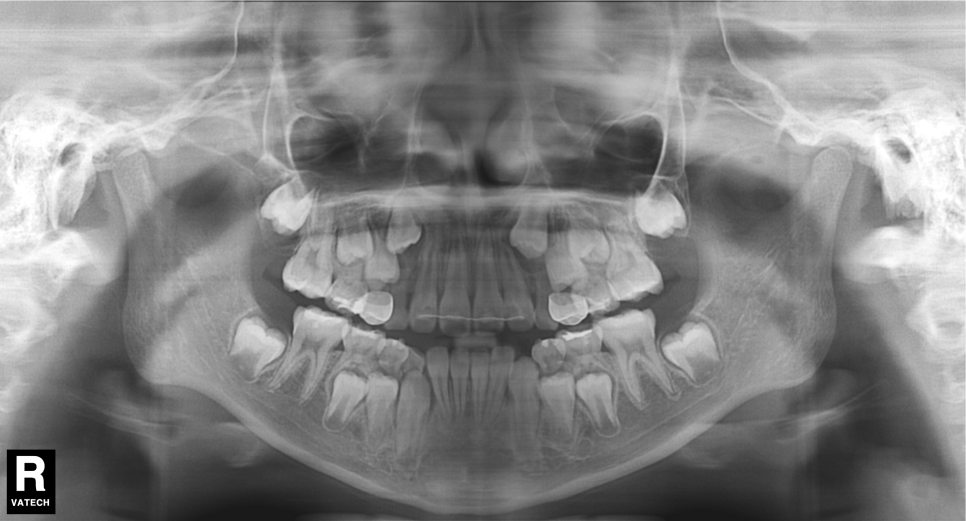

환자분의 상태를 살펴보면

치아가 날 공간이 부족하거나 치아가 나오는 방향에서

앞니가 앞으로 나오고 다른 치아가 기울어지면서

거꾸로 물리는 현상이 발생한 걸로 보여요.

어린이 치아교정 상태

투디 치과(2D 치과)